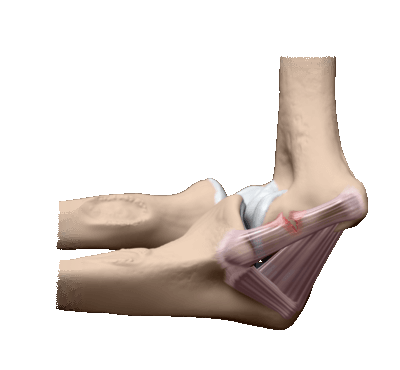

Повреждение этого элемента довольно редкое и относится больше к спортивным. Они могут быть частичными или полными. При первом варианте весь курс обходится консервативными методами и продолжается в течение 2-3 недель. В этот период конечность пациента иммобилизована.

Травма связок локтевого сустава

При полном разрыве необходимы манипуляции по сращиванию связок. Для этого на задней стороне локтя делается рассечение, и соединительная ткань сшивается мелкими участками.